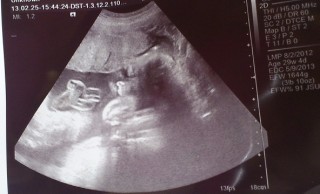

29w4d頭73.7㎜ お腹257.2㎜ 大腿骨51.1㎜ 体重1442g。 横顔が主人の寝顔に似てます(^^)d 前置胎盤が低置胎盤に!(*^^*) 喜んだのも束の間で、次の日出血があり入院になってしまいました。(現在入院中)張りが強かったようです。赤ちゃんは元気でほっとしてます。とにかく安静☆

体重1245グラム。やや小さめらしいが健康の範囲で経過も良好!逆子の心配なくちゃんと頭位だった☆エコー写真はいいの撮れなくて背骨の写真だけ^^: